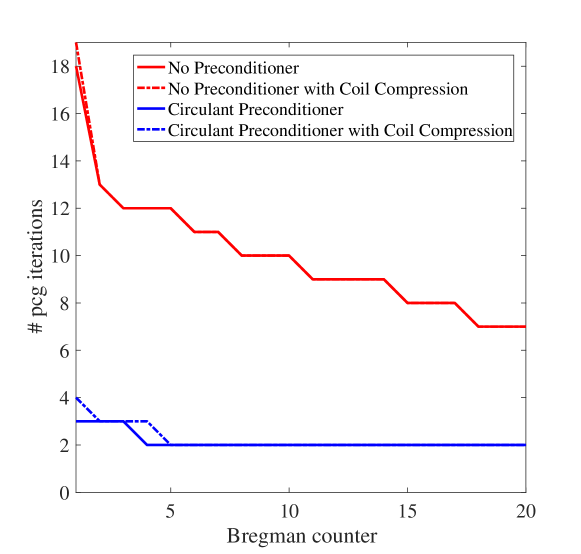

Coil compression can be applied to reduce the reconstruction time. The effect on the number of iterations required for PCG when applying coil compression on the measurement data is expected to be the same, as it only slightly affects the structure or content of the system matrix . Figure 7 illustrates the result on the required iterations when half of the coils are taken into account. Only a small discrepancy is encountered for the first few iterations, which demonstrates that coil compression and preconditioning can be combined to optimally reduce the reconstruction time.